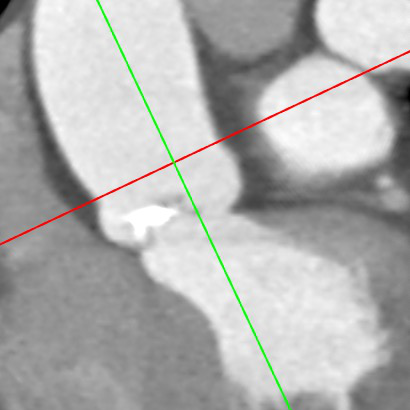

CT评估:

瓣环周长74.6mm,左室流出道周长79.4mm,左冠高度9mm(瓣叶长14mm),右冠高度10mm(瓣叶长11mm),窦宽31/29/30mm,STJ距瓣环高度14.5mm,最大直径约27.6mm。

横切面

纵切面